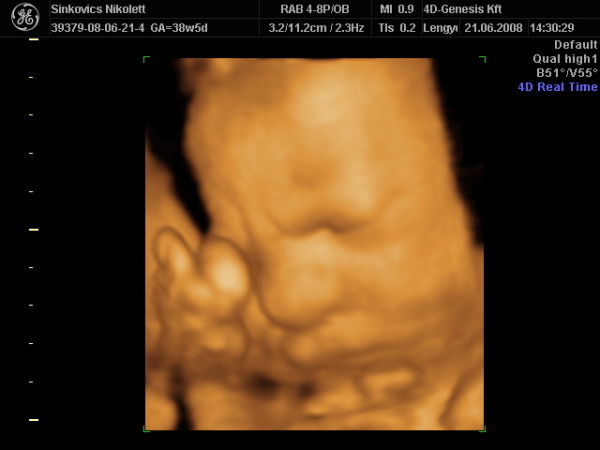

De majd ma, a Genesisben talán megmondják, hogy áll a méhlepény érettsége.